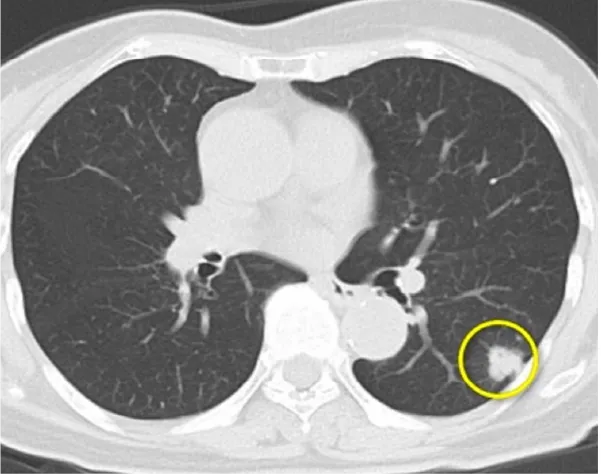

① 肺癌

我が国において、「がん」によって亡くなった人は1981年に脳卒中を抜いて第1位となり、現在、およそ3人に1人は「がん」によって亡くなっています。その中でも肺癌の増加は特に著しく、男性は1993年に胃癌を抜いて第1位に、女性においても大腸癌とともに増加して胃癌を抜いて第2位に、全体においても1998年に胃癌を抜いて第1位となりました。

肺癌の治療については、迅速かつ的確な診断を基に、その肺癌の種類(組織型)や進行度によって適切な治療が必要となります。肺癌の治療には「手術」、「抗癌剤治療」、「放射線療法」と大きく分けて3種類あり、肺癌の種類や進行度によっては、これらの治療を組み合わせた「集学的治療」が必要となります。